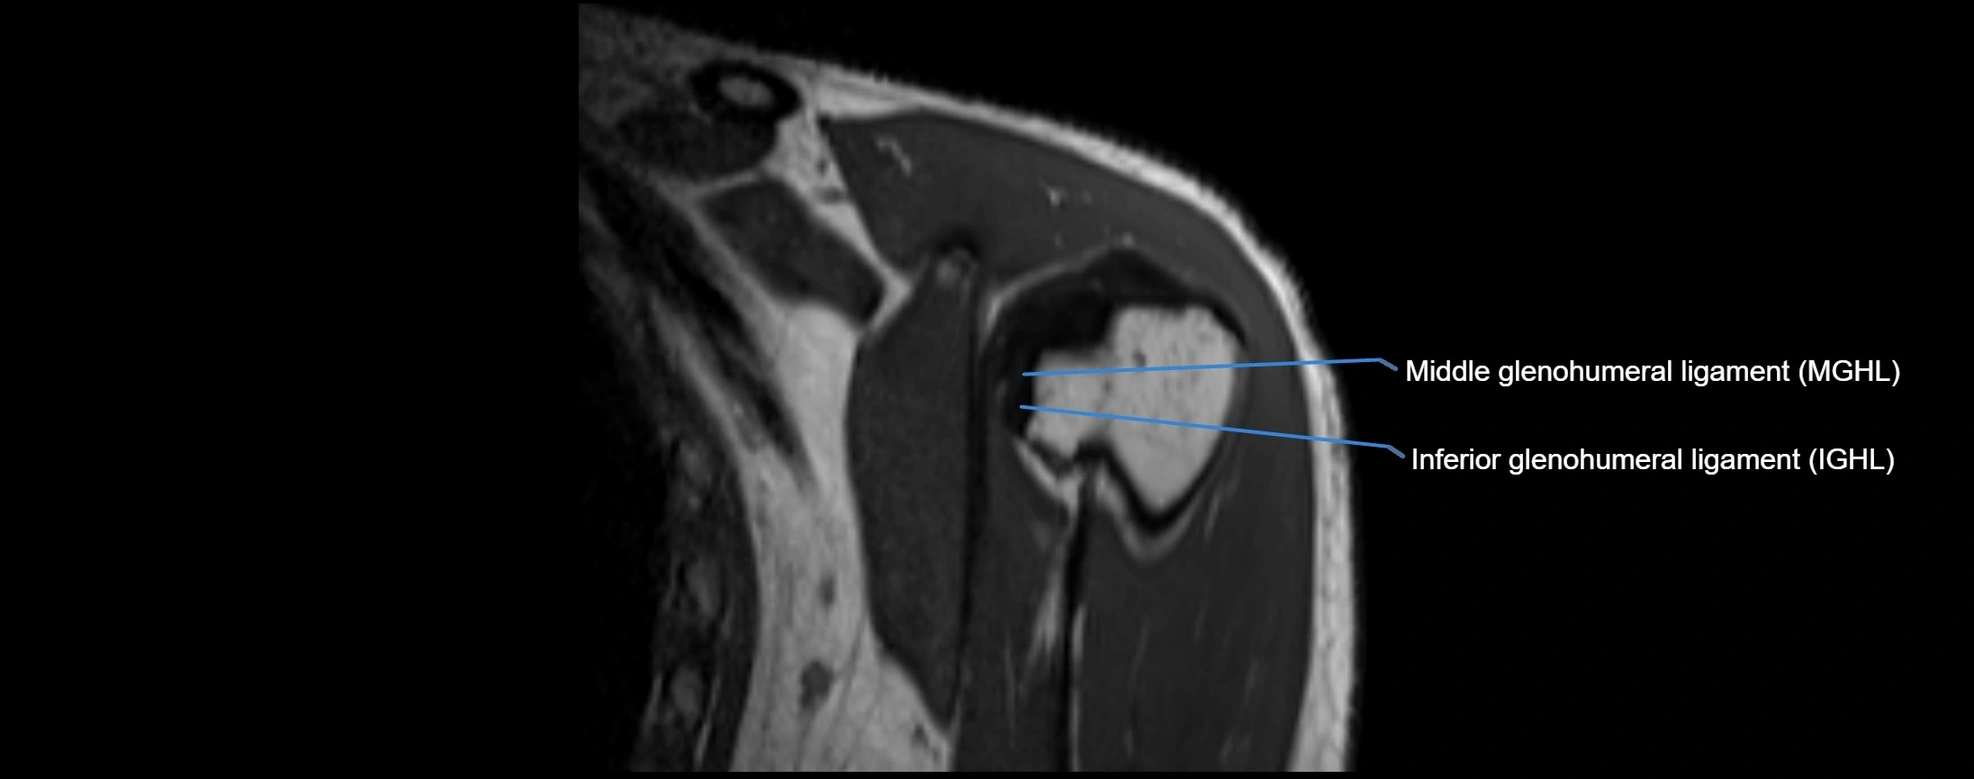

MRI images

image